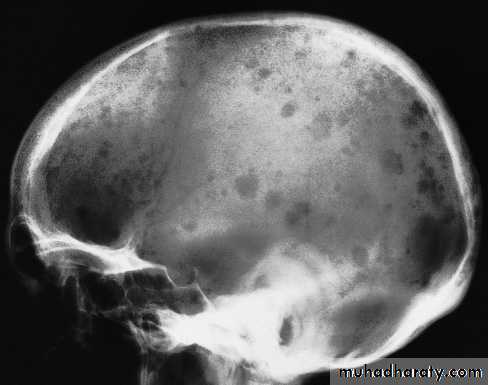

Skull X-rayBony configuration and shape

Bone densityAny Lytic lesion

Any fracture

Any calcification

Diploë, pituitary fossa, paranasal sinuses, orbits

The sutures

Langerhans histiocytosis